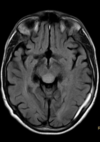

30 anos

Esclerose múltipla